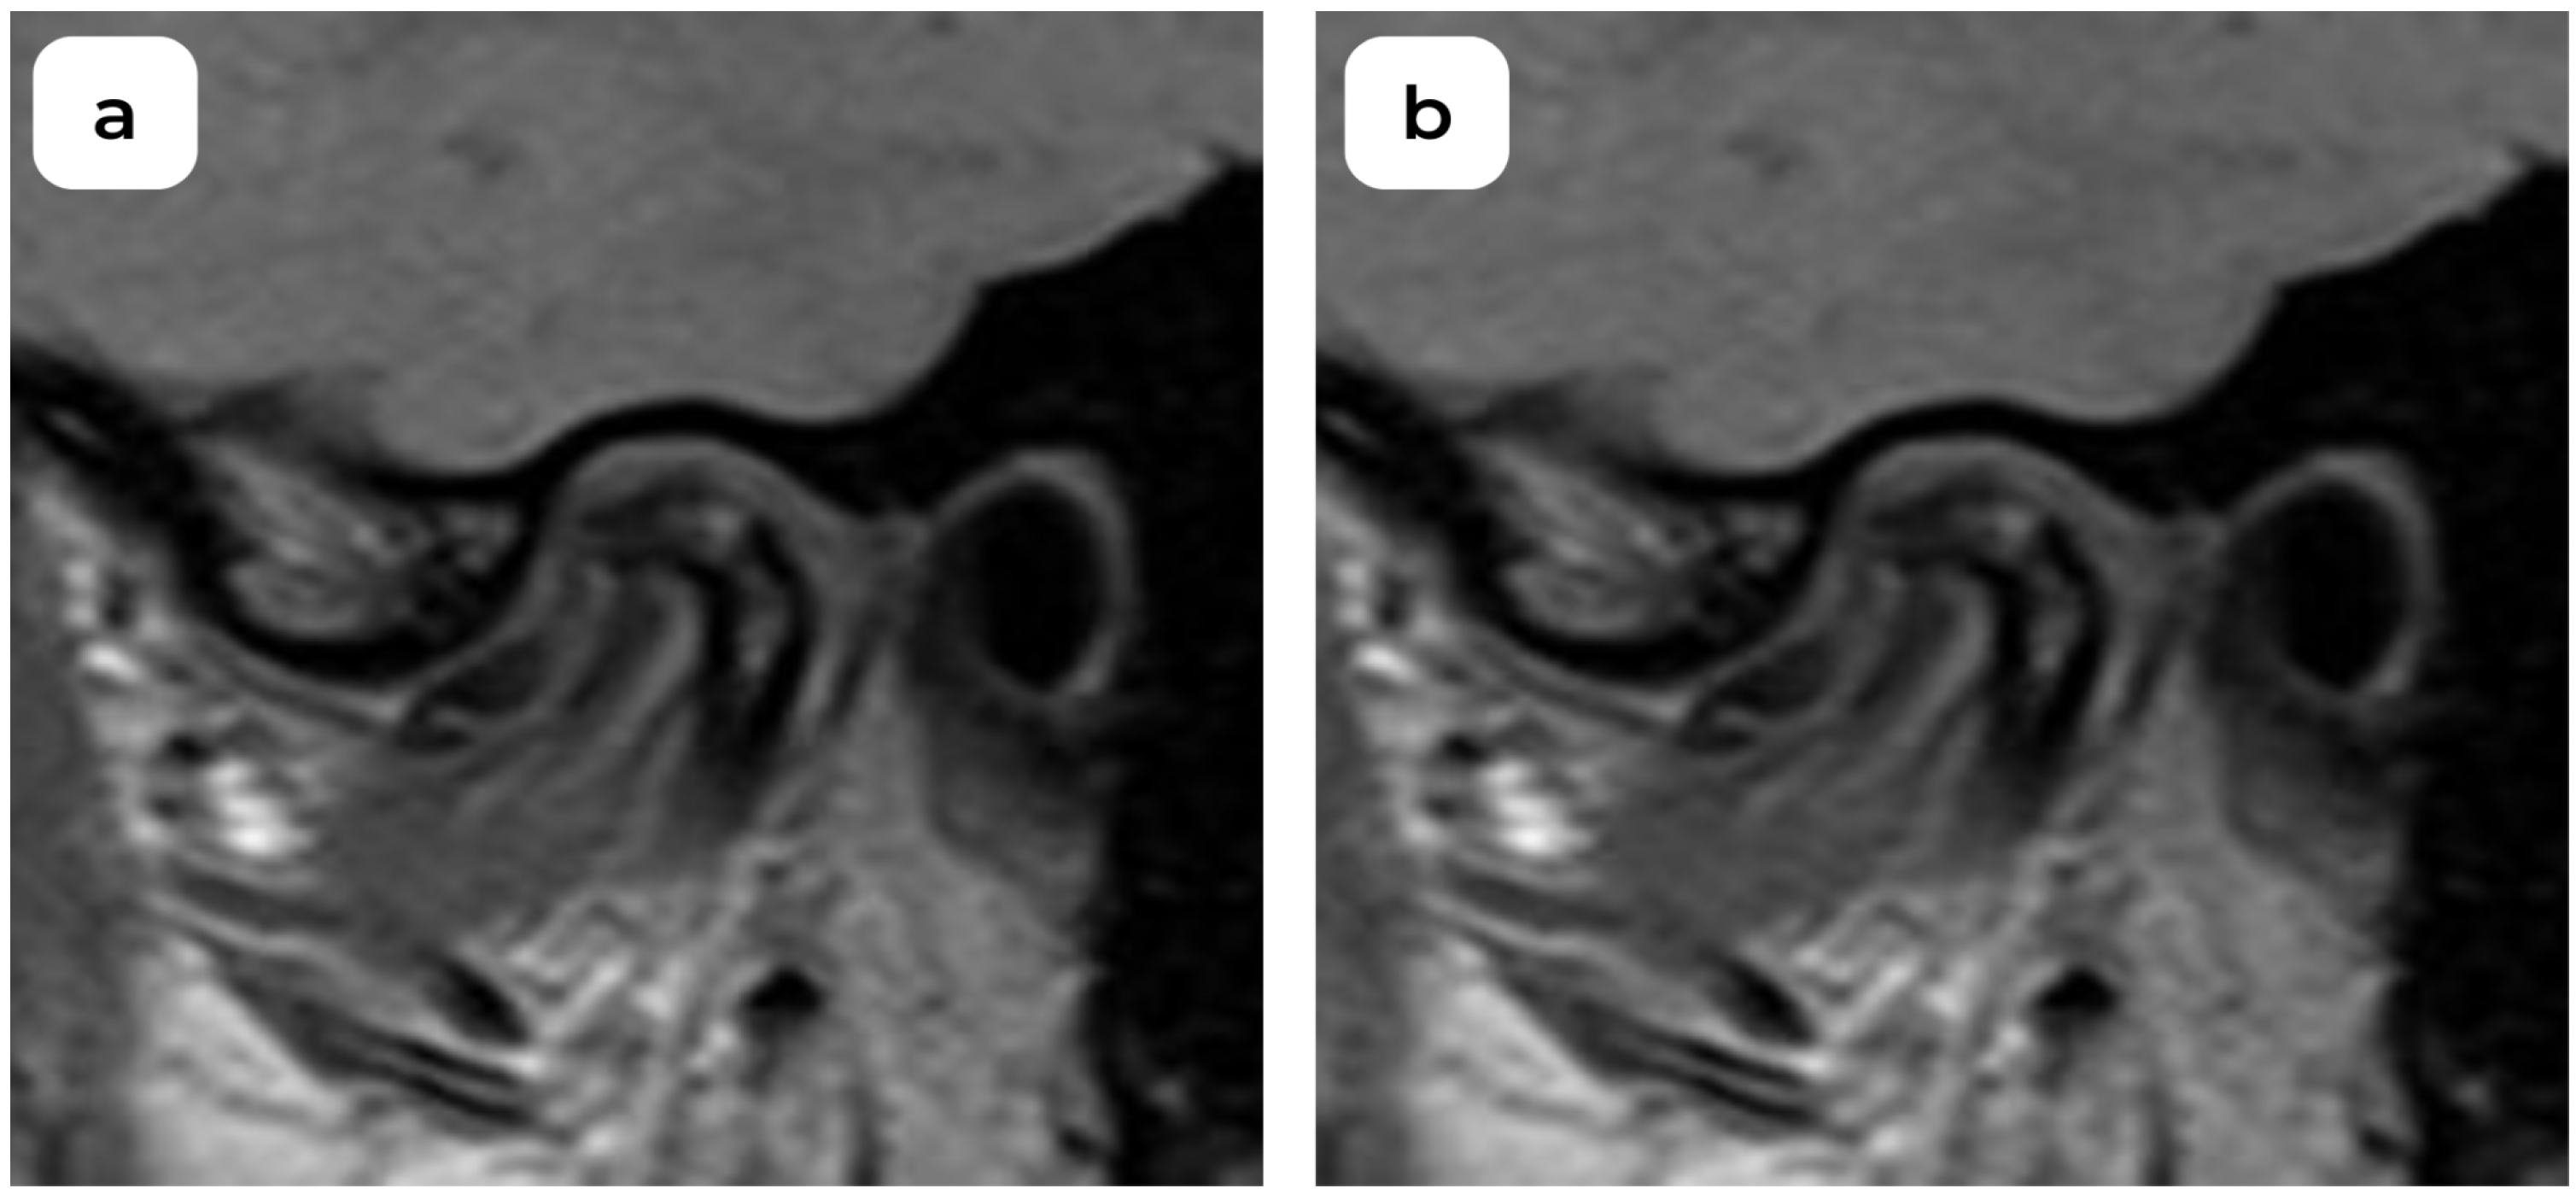

An Examination of Temporomandibular Joint Disc Displacement through Magnetic Resonance Imaging by Integrating Artificial Intelligence: Preliminary Findings